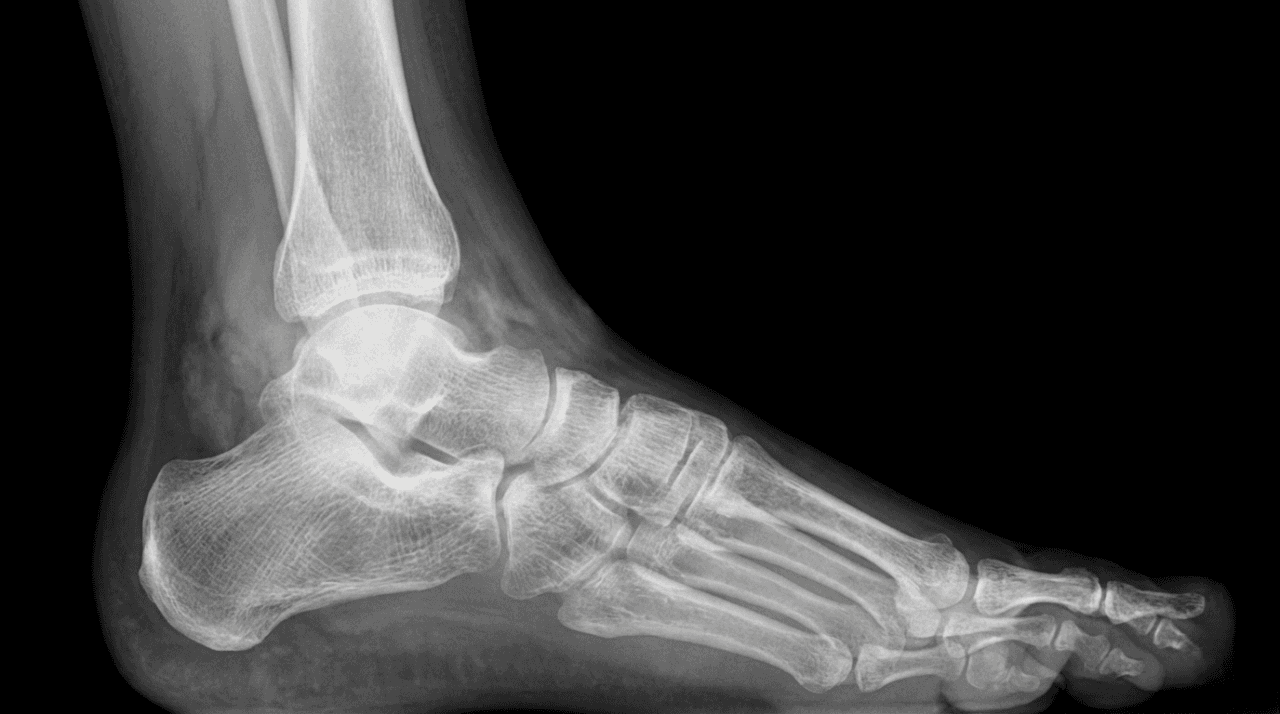

Comprehensive Foot & Ankle Care in Dubai

Dr. Farid Ghasemzadeh Mojaveri is a distinguished foot and ankle surgeon in Dubai, known for his expertise in advanced lower limb reconstruction and trauma care. As a board-certified consultant with affiliations at leading institutions like King's College Hospital Dubai, his practice is centered on providing meticulous diagnosis and evidence-based treatment for patients suffering from acute injuries, sports-related conditions, and degenerative diseases of the foot and ankle.

Expert Diagnosis and Treatment for All Foot & Ankle Conditions

As a highly specialized foot and ankle specialist, Dr. Farid offers advanced care for the full spectrum of conditions, ensuring you receive the most targeted and effective treatment, establishing him as one of the top foot doctors in Dubai.